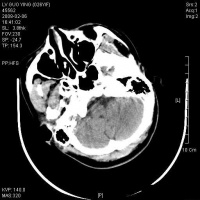

脑干含有大部分的脑神经核(除了嗅神经视神经),全身感觉、运动传导束,及呼吸循环中枢,脑干网状结构参与和维持意识清醒。故损伤后出现…… 1.意识障碍 原发性脑干损伤病人,伤后常立即发生昏迷,轻者对痛刺激可有反应,重者昏迷程度深,一切反射消失。如有昏迷

脑干损伤CT图

持续时间较长,很少出现中间清醒或中间好转期,应想到合并颅内血肿或其他原因导致的继发性脑干损伤。